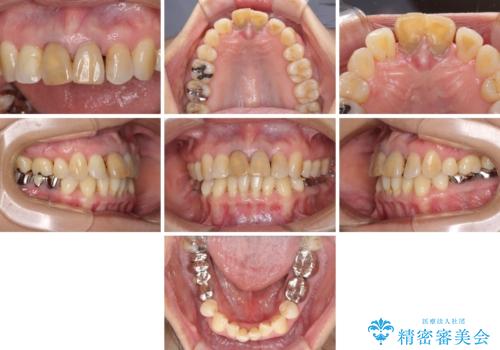

- 上の前歯の変色と、下の前歯のデコボコを気にして来院された患者様です。

前歯はオールセラミッククラウンに補綴することとしました。

補綴治療に先立ち、下顎前歯の部分矯正を行い、前歯の咬み合わせの安定性向上を図りました。

当初は上顎の補綴治療のみを希望されていましたが、奥歯にブリッジなど補綴物が多くあり、前歯も変色しているため、治療費が高額となってしまうことが懸念されました。

相談の上、最も気になっている前歯の部分矯正と補綴治療により口元の改善を図ることとしました。

審美面と合わせて清掃性も改善され、患者様には大変満足していただきました。